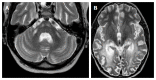

We describe common and less common diseases that can cause magnetic resonance signal abnormalities of middle cerebellar peduncles (MCP), offering a systematic approach correlating imaging findings with clinical clues and pathologic mechanisms. Myelin abnormalities, different types of edema or neurodegenerative processes, can cause areas of abnormal T2 signal, variable enhancement, and patterns of diffusivity of MCP. Pathologies such as demyelinating disorders or certain neurodegenerative entities (e.g., multiple system atrophy or fragile X-associated tremor-ataxia syndrome) appear to have predilection for MCP. Careful evaluation of concomitant imaging findings in the brain or brainstem; and focused correlation with key clinical findings such as immunosuppression for progressive multifocal leukoencephalopahty; hypertension, post-transplant status or high dose chemotherapy for posterior reversible encephalopathy; electrolyte disorders for myelinolysis or suspected toxic-drug related encephalopathy; would yield an appropriate and accurate differential diagnosis in the majority of cases.